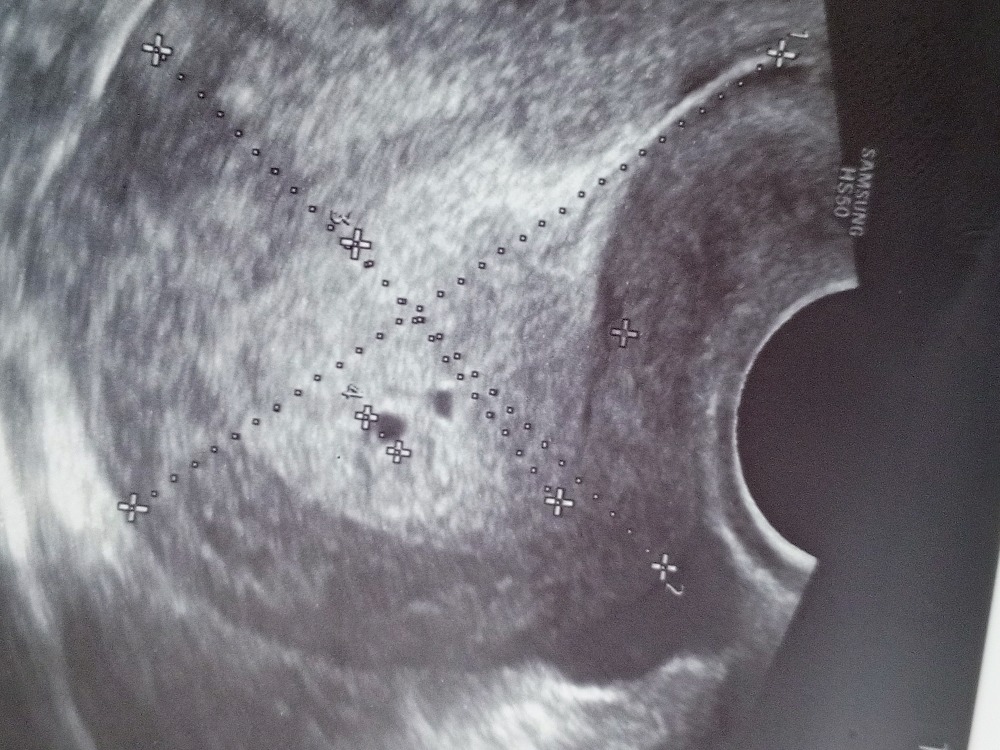

В 4 акушерских недели пя по УЗИ не видно,в 4,5 недели оно 2-3 мм и выглядит на фото как точка,пя от 5 мм это уже срок 5 недель,а у вас на фото и жм виден,ну какие 4 недели ? Желточный мешочек появляется в 5+ акушерских А 4 от зачатия не ставят,на таком сроке эмбрион есть и ставят акушерский срок по его размеру, эмбриональный срок ставят только максимум 3 недели,вот мое УЗИ пя 8 мм и жм и 3 недели,вот у меня срок от зачатия стоит на этом УЗИ это получается 5 акушерских было Изображение